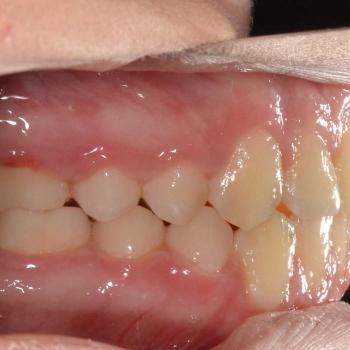

Csenge és édesanyja még vegyesfogazati időszakban, az egyetemen kerestek fel többszörös funkciós és esztétikai problémák miatt. Az első vizsgálat alkalmával súlyos nyitottharapást, keresztharapást, középvonal eltolódást, Angle II. osztályú eltérést, nyelvlökéses nyelést, helyhiányt diagnosztizáltunk, illetve elképesztő ritkaságként felcserélődött szemfog-kisőrlő csírákat találtunk a jobb oldalon.